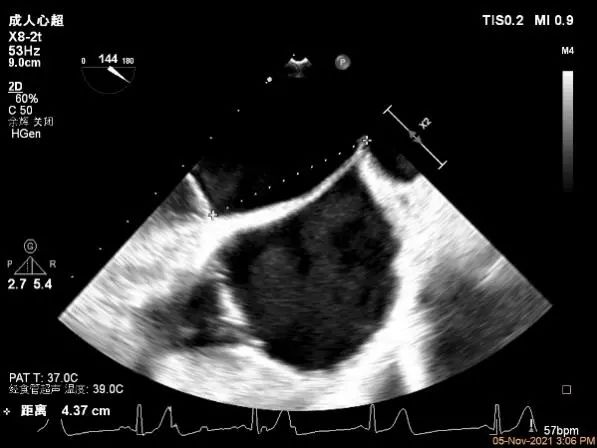

确定房间隔穿刺点:略靠前,3D视图2点位

穿刺点高度测量:4.37cm

Multivue测量大鞘长度2.34cm